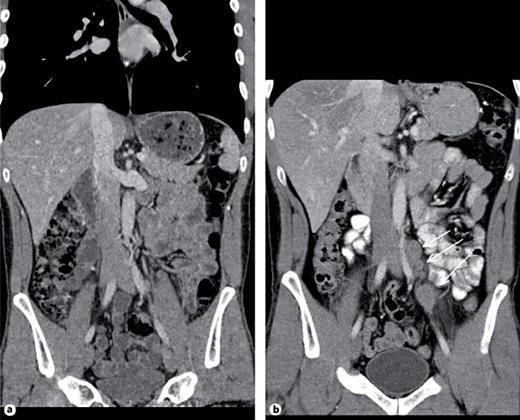

3rd patient: this 31-year-old patient underwent orchiectomy for testicular seminoma (pT3, CS1). Although markers were negative and no metastases were detected radiologically (Fig. 2a), the patient received adjuvant single-shot carboplatin therapy because of spermatic cord invasion of the primary and on grounds of personal choice of the patient. Twenty-six months thereafter he presented with a bulky retroperitoneal relapse (Fig. 2b). He was salvaged with 3 courses of BEP (bleomycin, etoposide and cisplatin) chemotherapy. It is to be noted here that the miR371a-3p level was at RQ = 3081.8 before orchiectomy and it continued to remain elevated at RQ = 351.8 five days after orchiectomy.

Then, no further decrease was recorded. At the time of the clinically apparent relapse, the level had risen to RQ = 4240.3 and it decreased to normal levels at the completion of salvage therapy and remained stable during the later course. This case was briefly reported previously [13].